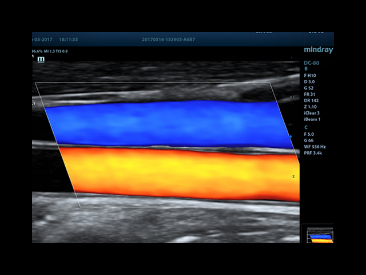

CCA and Jugular Vein